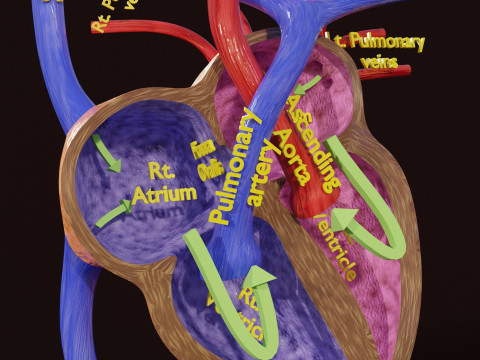

The model meshes include adult circulation versus circulation in Tetralogy of Fallot (TAF), arrow labels and text labels. The blood flow in a patient with Tetralogy of Fallot is outlined in this model. To contrast it to normal blood circulation a separate model of normal circulation is included. The Tetralogy of Fallot (OVER RIDING OF AORTA, PUL STENOSIS, VENTRICULAR SEPTAL DEFECT, RIGHT VENTRICULAR HYPERTROPHY), fossa, ligament teres , venosus, and arteriosus are duly depicted with proper labelling and blood flow directional arrows. Excellent model for teaching, demonstration and knowlegde of human body. The models include both procedural and image textures blend files separately. The texture file include diffuse, roughness and normal png and jpeg based on non overlapping UV maps.